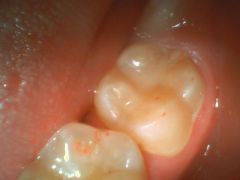

二次カリエス

(一度治した虫歯がまた虫歯になる事)

- シーラント部から虫歯になった例です。

シーラントとは?

虫歯予防の為、歯を削らずに埋める治療です。